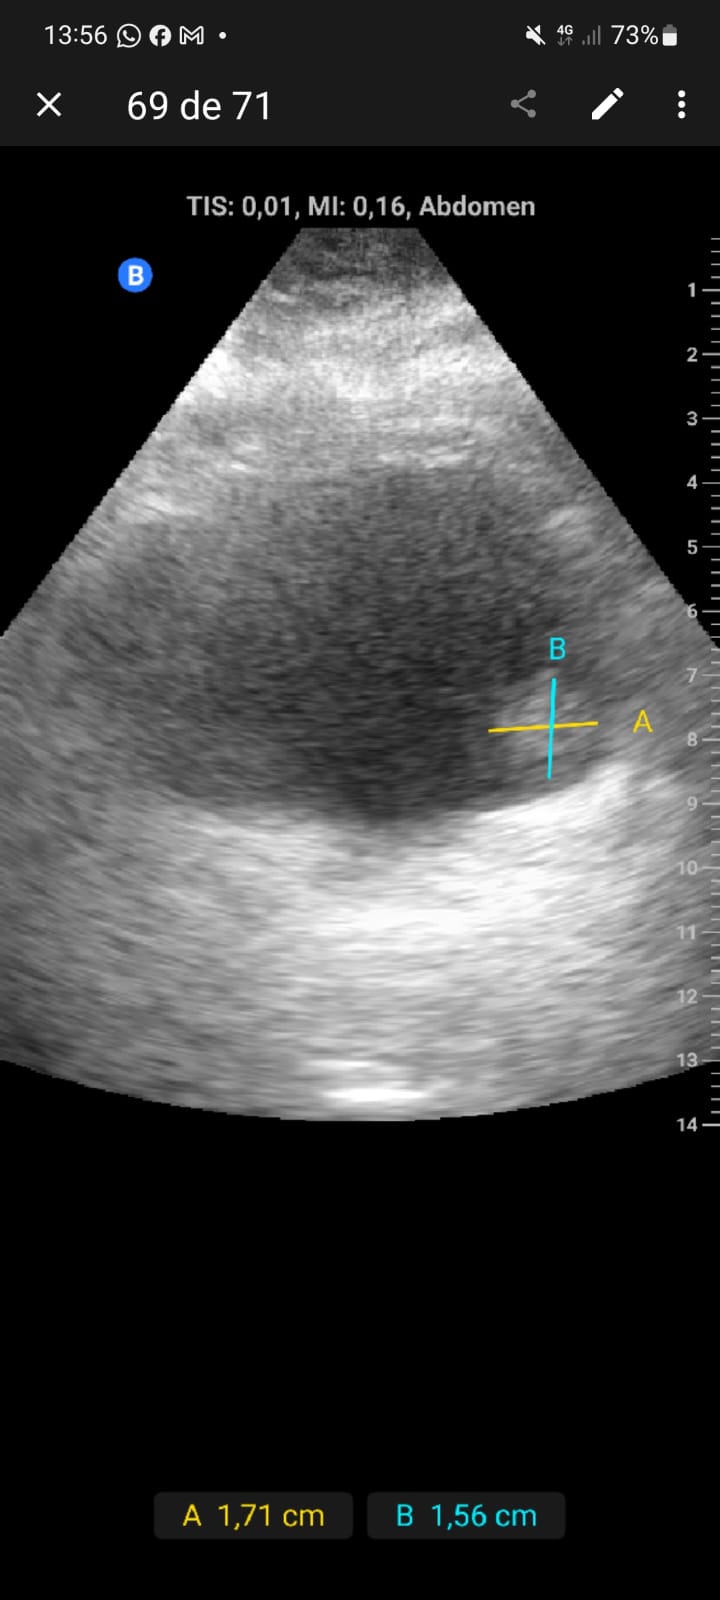

Exfumador, HTA, hipercolesterolemia, cirrosis hepática por alcohol. Hombre de 58 años que refiere episodio de hematuria macroscópica hace dos semanas, coincidiendo con un esfuerzo físico intenso el día previo. No presenta disuria, fiebre, poliaquiuria, ni dolor. En controles posteriores, no había recurrencia de hematuria y el paciente se encontraba asintomático.Exploración física sin hallazgos relevantes. Ecografía realizada en consulta en apenas 5 minutos mostró una masa en la cara lateral izquierda de la vejiga, de 1,5 x 1,3 cm, con características sugerentes de lesión tumoral superficial.

Lesión sólida, pediculada, de bordes definidos y fronda larga en la cara lateral izquierda de la vejiga.

Se sospechó un tumor vesical; pólipo vesical. Urología confirmó la lesión mediante cistoscopia, describiendo una masa papilar superficial de 2 cm en la pared lateral izquierda.